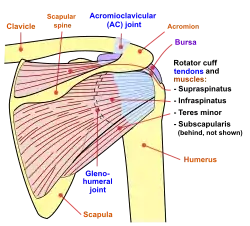

Rotator cuff

The rotator cuff is an anatomical term given to the group of four muscles and their tendons that act to stabilize the shoulder.[3] These muscles are the supraspinatus, infraspinatus, teres minor and subscapularis and that hold the head of the humerus in the glenoid cavity during movement.[3] The cuff adheres to the glenohumeral capsule and attaches to the head of the humerus.[3] Together, these keep the humeral head in the glenoid cavity, preventing upward migration of the humeral head caused by the pull of the deltoid muscle at the beginning of arm elevation. The infraspinatus and the teres minor, along with the anterior fibers of the deltoid muscle, are responsible for external rotation of the arm.[6]

The four tendons of these muscles converge to form the rotator cuff tendon. This tendon, along with the articular capsule, the coracohumeral ligament, and the glenohumeral ligament complex, blend into a confluent sheet before insertion into the humeral tuberosities.[7] The infraspinatus and teres minor fuse near their musculotendinous junctions, while the supraspinatus and subscapularis tendons join as a sheath that surrounds the biceps tendon at the entrance of the bicipital groove.[7]

In addition to the four muscles of the rotator cuff, the deltoid muscle and teres major muscles arise and exist in the shoulder region itself.[3] The deltoid muscle covers the shoulder joint on three sides, arising from the front upper third of the clavicle, the acromion, and the spine of the scapula, and travelling to insert on the deltoid tubercle of the humerus.[3] Contraction of each part of the deltoid assists in different movements of the shoulder - flexion (clavicular part), abduction (middle part) and extension (scapular part).[3] The teres major attaches to the outer part of the back of the scapula, beneath the teres minor, and attaches to the upper part of the humerus. It helps with medial rotation of the humerus.[3]